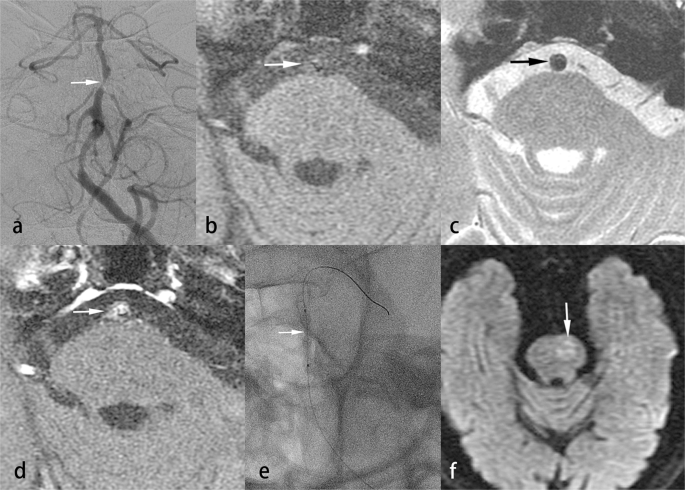

The clinical and MR results of the hard and soft lesion groups are shown in the Table 2. Patients in the hard lesion group more frequently had hyperlipidemia (8/16 [50%] vs 1/15 [6.7%], P = 0.0155) and a significantly higher PP (atm) (6.3 ± 0.9 [5.0–7.0] vs 3.1 ± 0.6 [2.0–4.0], P < 0.0001). The diagnosis of VBS was also significantly related to the hardness of the lesions (P < 0.0001). Hard lesions were noted in those with atherosclerosis and DA but not in those with dissection (Figs. 1, 2). For the soft lesion group, dissection was the most common diagnosis (12/15, 80%) (Fig. 3). On T1WI of VW-MRI, iso- to low intensity signals were significantly more frequent than high intensity signals in the hard lesion group (11/16 [68.7%] vs 5/16 [31.3%]) and high intensity signals were significantly more common than iso- to low signals in the soft lesion group (14/15 [93.3%] vs 1/15 [6.7%], P = 0.0004). On axial DWI of the brain, diffusion through the stenotic segment of the vertebrobasilar artery was significantly more restricted in the soft lesion group (5/15 [40.0%] vs 1/16 [6.3%], P = 0.0373).

Soft lesion in a patient with dissection. A 44-year-old man suffered from recurrent headache and dysarthria for 1 week. Brain MRI showed multiple recent infarcts in the bilateral cerebellar hemispheres on DWI. Right vertebral angiogram showed acute dissection with 85% stenosis of the right distal vertebral artery (a). VW-MRI of the right distal vertebral artery showed a high-signal intramural hematoma on fat-suppressed T1WI (b, arrow) and T2WI (c, arrow) and focal strong enhancement of the intramural hematoma on contrast-enhanced fat-suppressed T1WI (d, arrow). During the PTAS, the PP was 3 atm. A 3.5 × 20 mm balloon-expandable stent was placed in the right distal vertebral artery. In a 4-year follow-up, CTA with curved multi-planar reconstruction showed good patency of the stent (e, arrow).